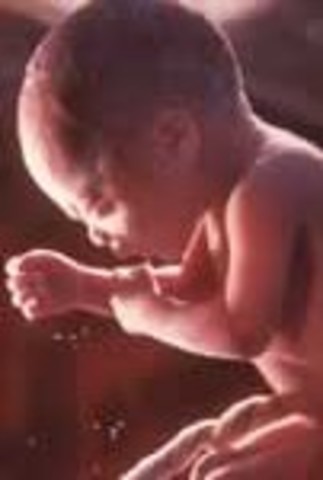

• Week 20 of the Second Trimester

Week 20 of the Second Trimester

This is the mid point in the pregnancy, the Fetus can now process outside noises and will become familliar with common voices.

Facts:

1)Baby now weighes about 11 ounces and is roughly 7 inches long.

2)The mother will probably start feeling the first fetal movements.